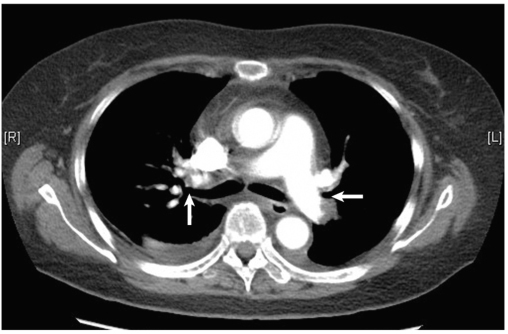

出院后2个月随访,胸闷、气短症状明显减轻,复查肺部CTA:双肺栓塞灶较前明显吸收(图2)。嘱长期利伐沙班抗凝,定期随访。

图2肺动脉CTA示抗凝治疗2个月后双侧肺动脉血栓大部分溶解吸收(白箭)